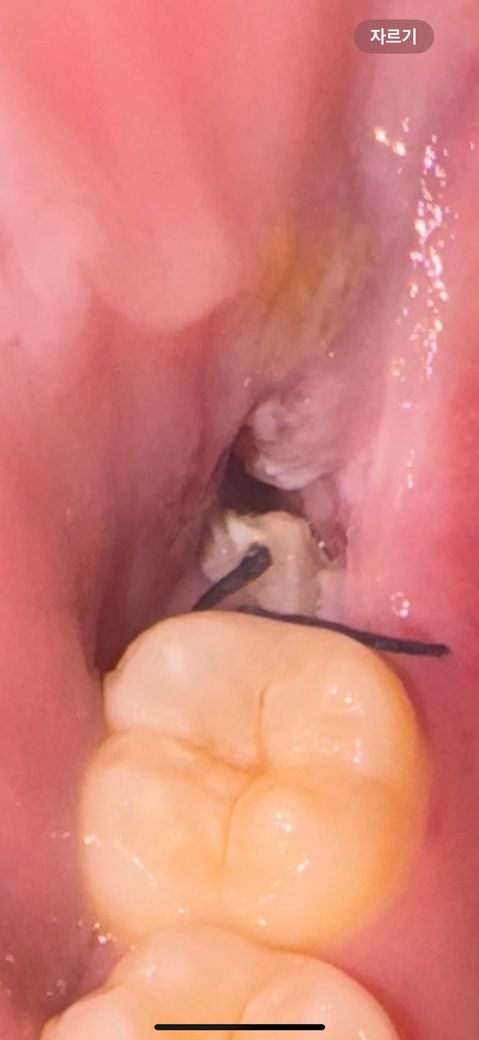

사랑니 발치 후 하얀 덩어리 질문이요..!!

27일 수요일 오후 12시쯤 오른쪽 아래 사랑니 절개 없이 뽑았는데 오늘 보니까 하얀색 덩어리들이 많이 껴있는데 잘 낫고 있는 과정일까요?? 아침에 일어났을때 살짝 욱식하고 시간 지나면 안아파요

사랑니를 발치하고 나면 발치한 부위에 이물질이 낄 수 있습니다. 음식물들이 들어가게 되면 사진과 같이 하얀색을 보일 수 있습니다. 사랑니를 발치한 부위에 이물질이 들어갔다고 하더라도 억지로 빼지 않는 것이 좋습니다. 무리하게 제거하려고 하다간 잇몸에 상처가 나고 치유가 늦어질 수 있기 때문입니다.

사랑니 발치를 하고나서 치유되는 과정중에 생기는 자연스러운 현상이니 물로 여러번 헹궈주시면될것같습니다.

발치 후 잇몸이 치유되는 과정에서 생기는 부산물(염증, 육아조직)입니다 발치 후 주의사항만 잘 지켜주세요